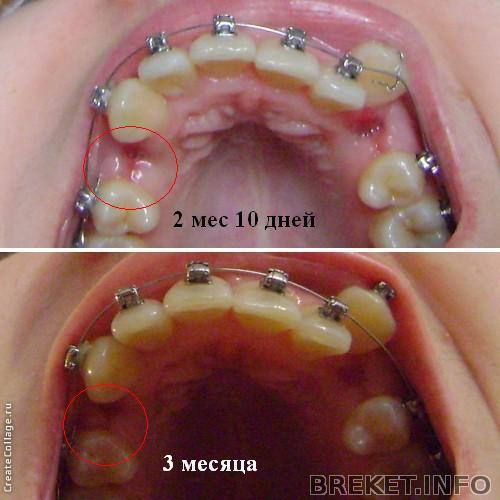

завтра 3 месяца - результаты

Решила отчитаться по результатам за 3 месяца - для многих эта дата считается значимой. Итак, что мы имеем: все еще первая дуга (менять уже точно 8 апреля), все еще неподключенный клык (на прошлом приеме его отвязали от дуги) и затягивающуюся дырку от четверки с одной стороны. Клык на этой стороне тянем эластичной цепочкой, но она чисто символическая, она болтается и почти не натянута. Ортша говорит, что так и надо, потому что если тянуть клык сильнее на тонкой дуге, зубы могут двигаться не так как надо. Так что клык по сути идет к пятерке сам, и неплохо идет (на фото видно, что расстояние сократилось)

А вот когда мне кажется, что ничего не меняется, я смотрю на этот коллаж

Мне кажется, или правда челюсть расширилась за 3 месяца?